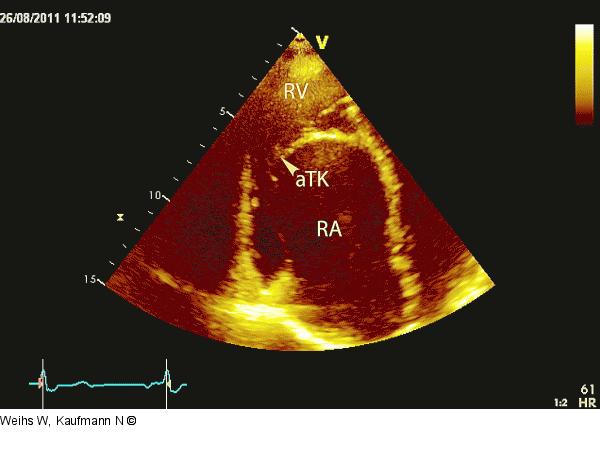

Abbildung 5: Rechter Ventrikel Apikale Darstellung des rechten Ventrikels (RV) und Vorhofes (RA). Durch die Verlagerung der Trikuspidalklappe ist ein erheblicher Teil des rechten Ventrikels atrialisiert. aTK = anteriores Trikuspidalsegel. |

Apikale Darstellung des rechten Ventrikels (RV) und Vorhofes (RA). Durch die Verlagerung der Trikuspidalklappe ist ein erheblicher Teil des rechten Ventrikels atrialisiert. aTK = anteriores Trikuspidalsegel. |